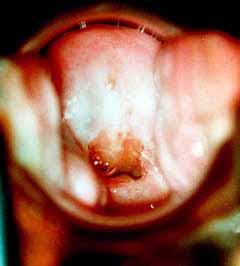

Κολποσκοπικές εικονες για τις αναγκες του forum.